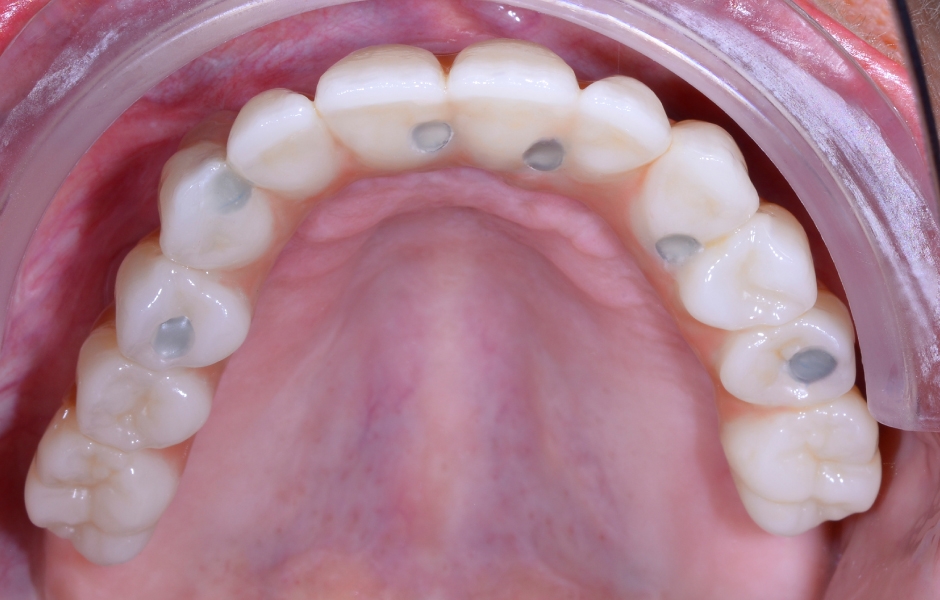

Obr. 26: Okluzální pohled na definitivní rekonstrukci s palatinálními šroubovými kanálky.

Obr. 27: Situace v horní čelisti po sejmutí provizoria.